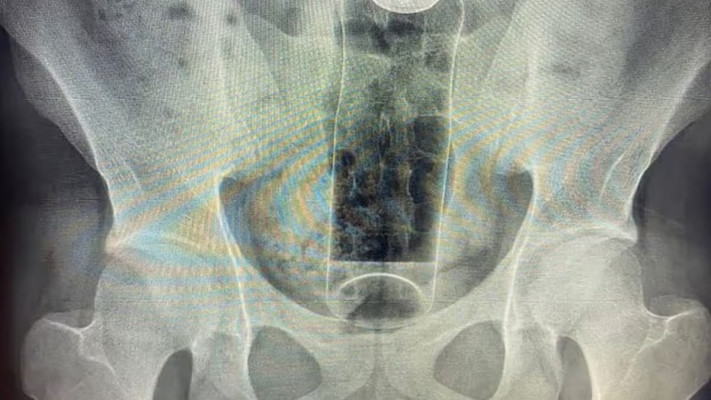

במקרה שמעלה חיוך עצוב, צעיר בן 19 בברזיל נדרש לעבור ניתוח חירום בבית חולים בסאו פאולו לאחר שפקק דאודורנט נתקע בתא המעיים שלו במהלך משחק מיני. הצעיר, שביקש להישאר בעילום שם, הובהל למרפאה עם כאבים עזים בבטן.

גבר הכניס דאודורנט לישבנו

גבר הכניס דאודורנט לישבנו | צילום: צילום מסך